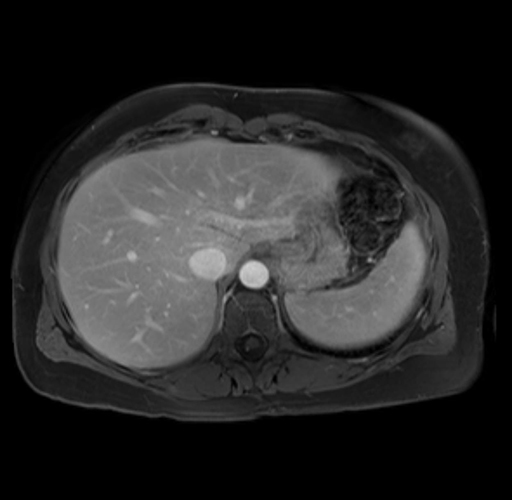

Imaging Analysis

Look through the patient's CT scan to identify any areas of concern for the necessary procedure.

Based on your CT findings, which issue(s) are present and would give reason for "planned slowing down moment(s)" in this case?